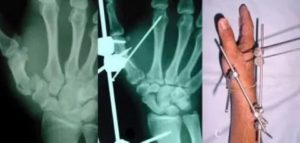

Хирургические методы лечения назначаются при осложненных переломах со смещением и предполагают госпитализацию пострадавшего. В ходе операции через ногтевую фалангу пациента вводится специальная спица, способствующая скелетному вытяжению обломков.

В наиболее тяжелых случаях проводится хирургическое вмешательство под действием общего наркоза. Кисть разрезается, проводится вправление и сопоставление костных фрагментов. Специалист придает кисти и пальцам правильное положение, после чего вводится спица. В завершение операции накладываются швы и фиксирующая гипсовая повязка.